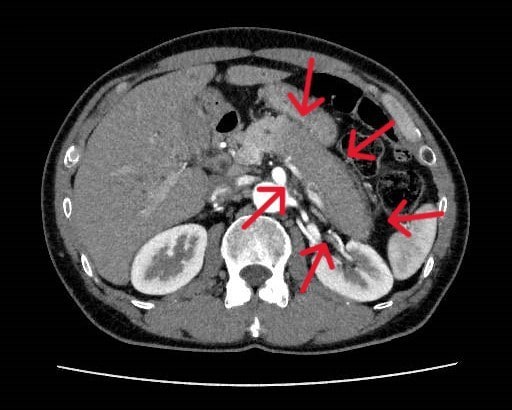

健診にて肝機能異常、皮膚黄染を認め、精査目的で当院消化器内科受診となった。今回実施されたdynamic CTではIgG4関連疾患を疑う所見が認められた。血液検査でもIgG4高値を示しており、IgG4関連硬化性胆管炎と自己免疫性膵炎が疑われ、ステロイドでの加療が開始された。

IgG4関連疾患とは血清IgG4高値とIgG4陽性形質細胞の浸潤、線維化による臓器の腫瘤性、肥厚性病変を呈する全身性慢性疾患である。診断は臨床的及び画像学的診断、血清学的診断、病理学的診断によって行われる。今回実施されたdynamic CTでは胆道狭窄と膵臓のびまん性腫大、膵辺縁部の被膜様構造の所見があり、IgG4関連疾患の診断に有用であったといえる。